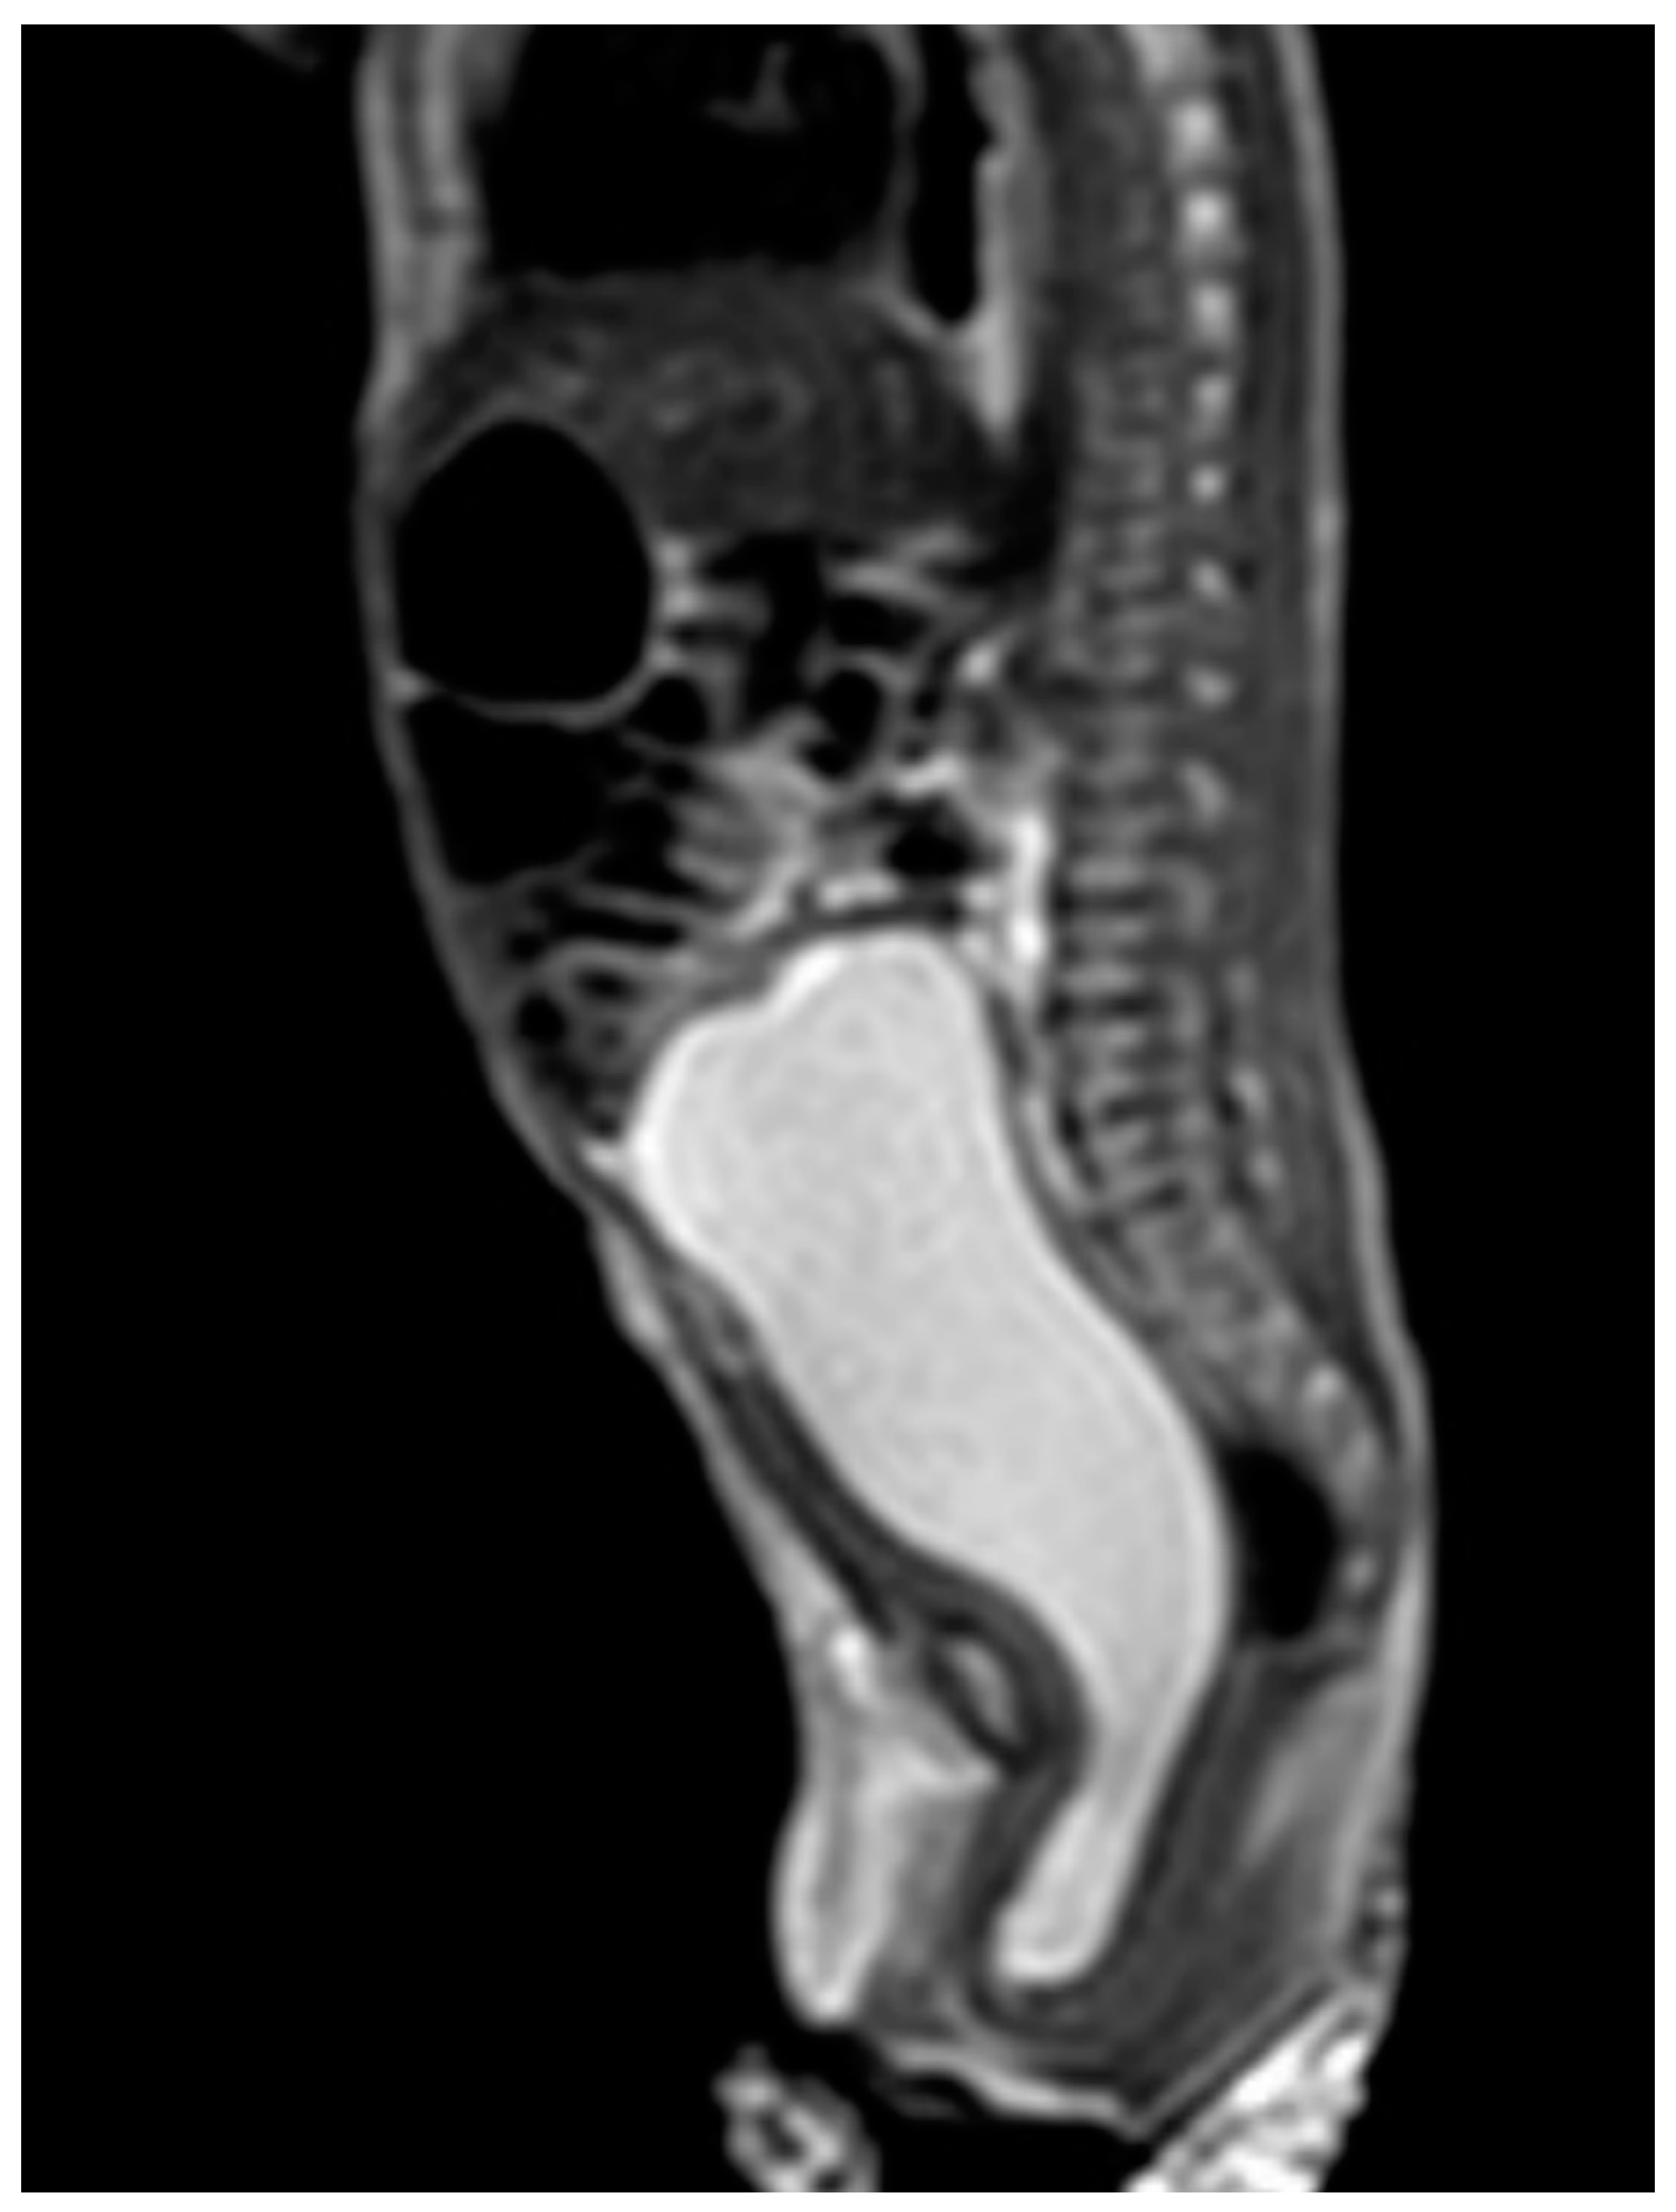

Case 1 was born at 36 weeks of gestation. An 8 cm cystic mass in the lower abdomen was detected on antenatal ultrasound from 32 weeks of gestation. The patient presented with a bulging mass over the vulva area. Magnetic resonance imaging (MRI) (Figure 1) showed a 9.1 cm cystic mass in the pelvic cavity, which extended to the vaginal orifice and caused left hydroureter, suggesting an imperforated hymen. Hymenotomy with a cross excision was performed, and 50 mL of milky fluids was drained. The patient is now 4 years, 4 months old, healthy without other medical issues.

Figure 1.

MRI of case 1: hydrometrocolpos manifested as an intraabdominal huge cystic mass.